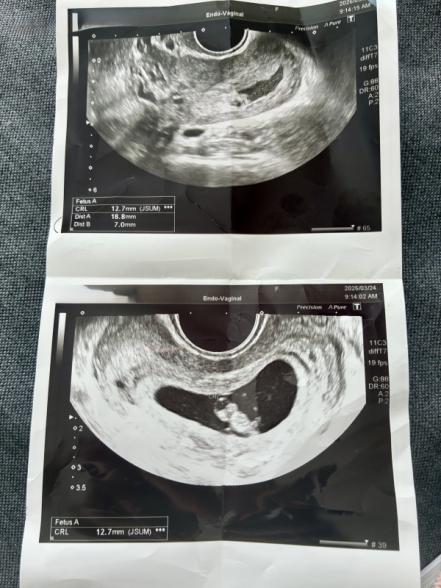

妊娠7週です。先日の健診で子宮内に出血があると言われました。赤ちゃんは順調に育っており、心拍確認もできました。特に安静制限も言われず薬も処方されず、1週間後に予定日と母子手帳の手続きするねといわれました。茶色の出血がでるかもしれないねと言われていますが、今のところ腹痛や出血なく経過しています。絨毛膜下血腫でしょうか?安静にとも言われていませんが、普通に生活していいのでしょうか?上が血腫で下が赤ちゃんです。

お写真からですと、絨毛膜下血腫なのかは、はっきりとは分かりませんが、子宮内に出血があると言われ、ご心配になりましたね。

ですが、特に安静の指示がなく、出血があるかも、と言われた程度であれば、おそらくそれほどご心配なものではないように思います。どうしても出血の溜まりがあれば、吸収されるか、排出されるかしない限り、なかなか小さくならないと思いますが、いまお腹の痛みや出血がないのでしたら、普段通りに生活していただいて問題ないのではないかと思いますよ。もし安静度などご心配であれば、おかかりつけの産院にご確認なさってくださいね。